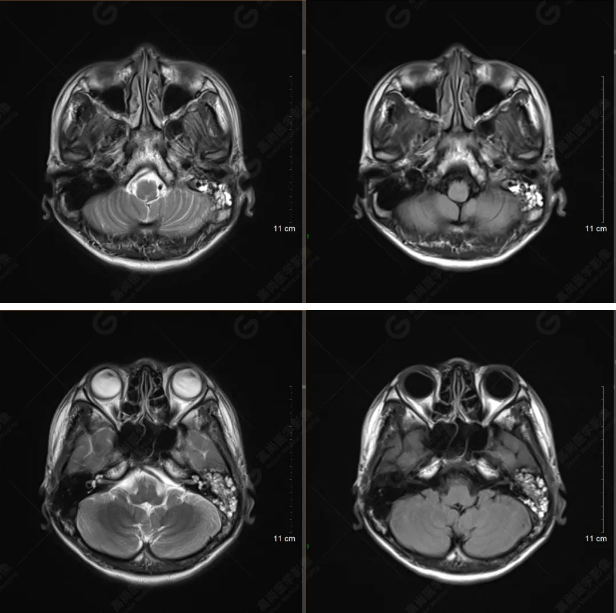

以下是平掃T2WI及FLAIR序列:

雙側(cè)大腦半球?qū)ΨQ,灰白質(zhì)對比正常,顱內(nèi)未見異常信號影。腦室系統(tǒng)未見擴(kuò)大,中線結(jié)構(gòu)居中。腦溝、裂未見增寬。幕下小腦、腦干未見異常。矢狀位示垂體形態(tài)、大小級信號未見異常。所示左側(cè)乳突內(nèi)見多發(fā)短T1長T2信號影。

顱腦MRI平掃未見明顯異常,左側(cè)乳突內(nèi)積血,建議補(bǔ)充SWI檢查。